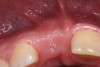

Two months after completion of the endodontic treatment of tooth No. 9, the patient presented with a chisel fracture about 2 mm apical to the cementoenamel junction (CEJ). The crown of tooth No. 9 was removed that day and Ca(OH)2 was replaced in tooth No. 8. Clinical photographs and radiographs were taken 3 months after removal of the coronal segment of No. 9 (Figure 3 and Figure 4). The missing crown of No. 9 was replaced with a temporary partial denture.

Fig 3. Age 10. Radiograph of teeth Nos. 8 and 9, 3 months after the fractured coronal segment of No. 9 was removed. Note the coronal level of the root relative to tooth No. 10.

Figure 3